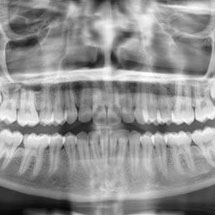

Panoramique dentaire

Il permet d’étudier la formule dentaire (nombre et position), la structure des dents et leur environnement (parodonte). Il permet de visualiser le fond des sinus (sinusite), et les articulations temporo mandibulaires (arthrose, déplacements).

On recherche surtout des lésions dentaires, des dents incluses, des kystes, des granulomes (infections), des anomalies osseuses ou des fractures.

Chez l’enfant, on analyse l’évolution de la dentition.